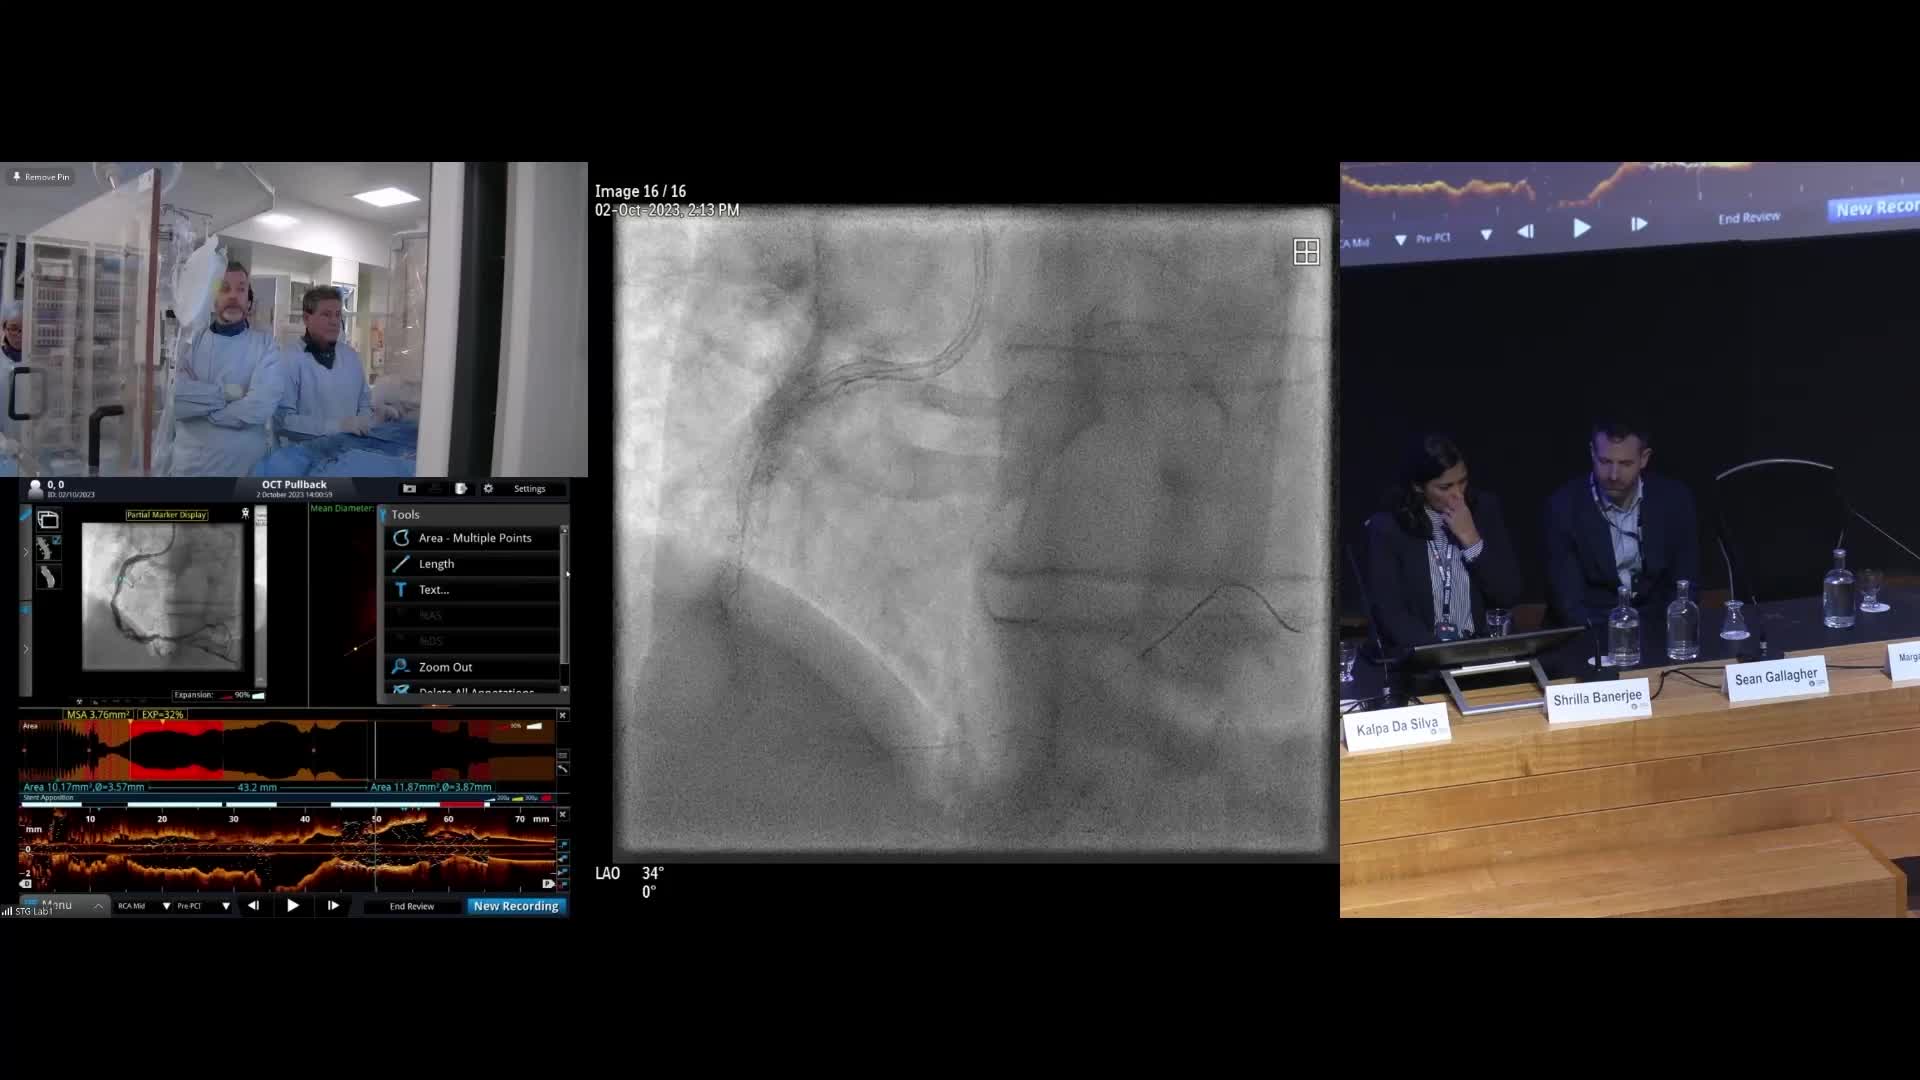

Optimal PCI London 2023

Welcome to Optimal PCI London 2023

Session 2: Coronary calcium – too hard to crack?